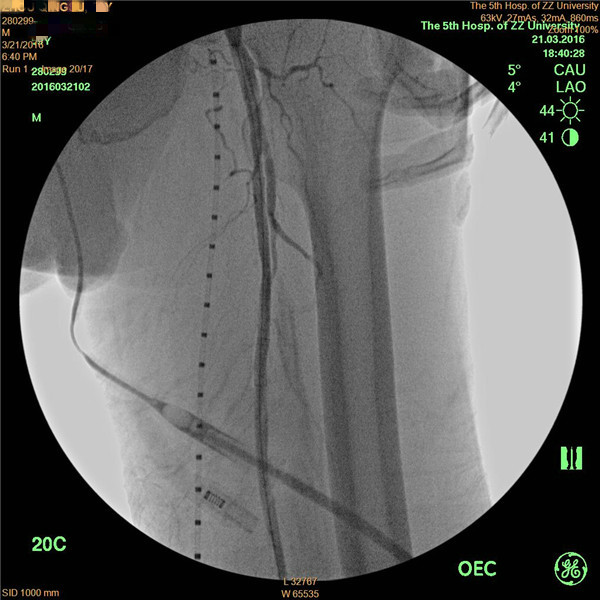

患者周先生,59岁,1年前无明显原因出现双侧小腿及足部发凉,活动后左足疼痛,3月前疼痛加重,出现左足第4及第5足趾发紫,并逐渐进展为足趾发黑、坏死,多处求医用药治疗,效果差,2周前左足疼痛进一步加重,并累及左足第3足趾发黑坏死,无法行走,严重影响了病人的生活质量(见图1)。慕名前来我院血管外科就诊。我院血管外科专家王兵教授为患者制定了详细的诊疗方案,下肢动脉CTA提示患者左侧股浅动脉多发粥样硬化斑块形成,管腔长段闭塞(见图2),明确诊断为“复杂下肢动脉硬化闭塞症”,积极术前准备后,王兵教授带领血管外科崔文军副主任、安乾主治医师、李攀峰医师给患者进行血管腔内介入治疗。术中DSA造影提示:股浅动脉长段闭塞,腘动脉通畅(见图3、图4)。单弯导管配合超滑导丝及微导丝,反复多次尝试顺行开通股浅动脉闭塞段均宣告失败,王兵教授决定采用逆穿技术,在DSA下穿刺腘动脉,成功后逆行置入单弯导管及超滑导丝,顺利开通股浅动脉闭塞段,逆行超滑导丝选入顺行单弯导管内,完成对接(见图5、图6),逆行导丝引出体外,引入球囊扩张股浅动脉闭塞段,股浅动脉闭塞段置入两枚金属裸支架后造影显示左下肢动脉全程通畅(图7、图8)。术后患者胫后动脉搏动恢复,静息性疼痛消失。 复查下肢动脉CTA:左下肢动脉血流通畅(图9)。

图5

图6